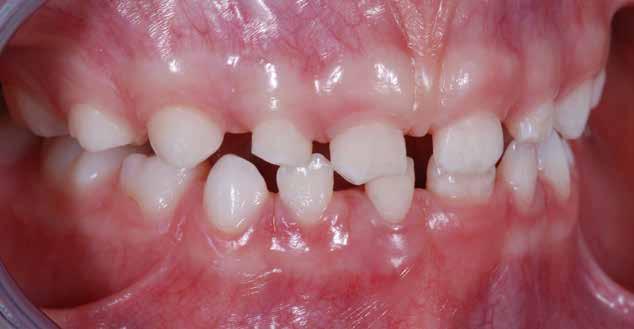

B.M. Bambina di sei anni e mezzo, con malocclusione scheletrica di II Classe, deep-bite over-jet elevato, lieve contrazione dell’arcata superiore, alterazione dell’eruzione dell’elemento dentale 21.

Fig. 122 > Immagine intraorale frontale.

Fig. 123 > Immagine intraorale laterale destra.

Fig. 124 > Immagine intraorale laterale sinistra.

69 68 ESTETICA FUNZIONE POSTURA Valori cefalometrici iniziali ANB ANB 6,20 Posizione del Mascellare SNA 84,20 Posizione della Mandibola SNB 78,00 Angolo Articolare SArGo 132,00 Angolo Goniaco ArGoMe 134,00 Angolo incisivo inferiore Corpo Mandibolare liMand 97,00 Angolo incisivo superiore Base Cranica Anteriore IsCran 107,00 Angolo Interincisivo II 123,00